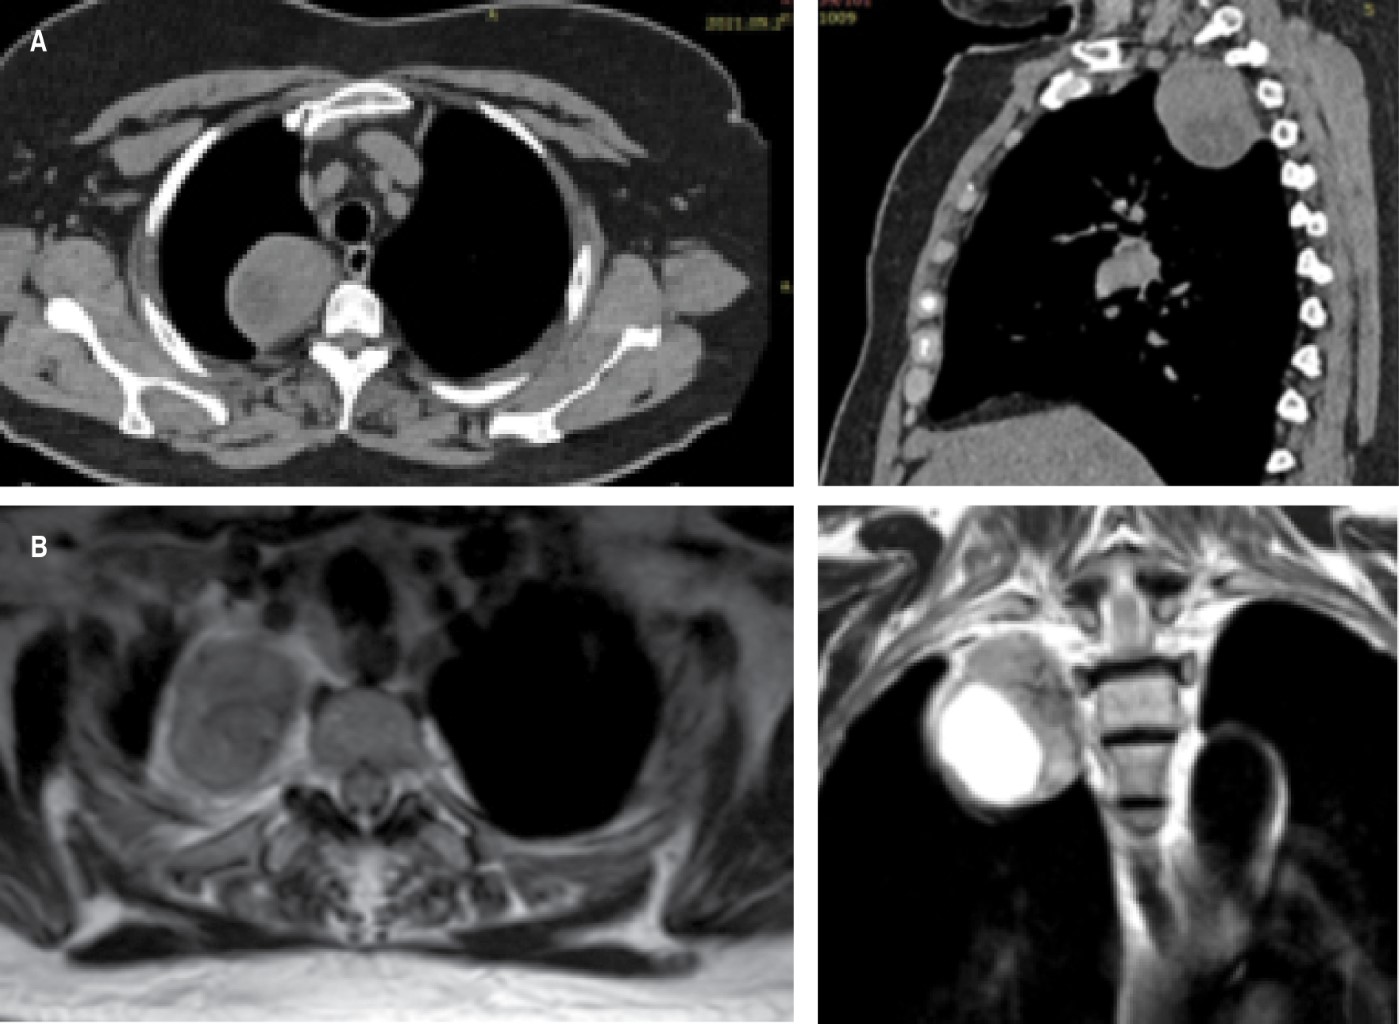

En los estudios de imagen, los tumores de vaina periférica son tumores bien definidos, hipodensos, con baja atenuación y realce al contraste en la tomografía computarizada (TC). En las imágenes por resonancia magnética (IRM) son isointensos en T1 e hiperintensos en T2.1 La resonancia magnética es el método más sensible para definir la presencia y extensión del componente intraespinal del tumor. Está indicada cuando el tumor está contiguo al foramen neural, cuando hay un foramen intervertebral ensanchado o cuando existe erosión de un cuerpo vertebral o un pedículo.5

Femenino de 67 años. Antecedentes de importancia: alergia a penicilina. Tabaquismo negado. Inició su padecimiento posterior a infección por SARS-CoV-2, donde se realizó una tomografía simple de tórax con hallazgo incidental de tumor de mediastino posterior (Figura 1A). Se completó estudio con resonancia magnética (Figura 1B) motivo por el que se envió al Servicio de Cirugía de Tórax del Instituto Nacional de Enfermedades Respiratorias Ismael Cosío Villegas, Ciudad de México. Exámenes preoperatorios y marcadores tumorales normales. Se decidió abordaje por VATS con dos puertos para resección del tumor (Figura 2A), con hallazgos de un tumor dependiente de la vaina nerviosa a nivel del segundo espacio intercostal, blanquecino, vascularizado, de 5 × 4 cm de diámetro (Figura 2B), el cual se resecó en su totalidad sin complicaciones. Evolución posquirúrgica satisfactoria, retirando el drenaje al tercer día, con adecuada expansión pulmonar. Reporte de patología de un tumor de vaina nerviosa periférica compatible con schwannoma, con inmunohistoquímica positiva a PS100 y enolasa. Seguimiento a seis meses sin evidencia de recidiva tumoral.

El schwannoma es un diagnóstico diferencial entre los tumores de mediastino posterior. Los estudios de elección para diagnóstico son la tomografía computarizada y la resonancia magnética que brindan detalles del nivel de involucro del tumor. El diagnóstico se apoya en las características por patología e inmunohistoquímica. El tratamiento es la resección quirúrgica completa, idealmente por abordaje mínimamente invasivo, lo que permite una adecuada supervivencia y baja recidiva.